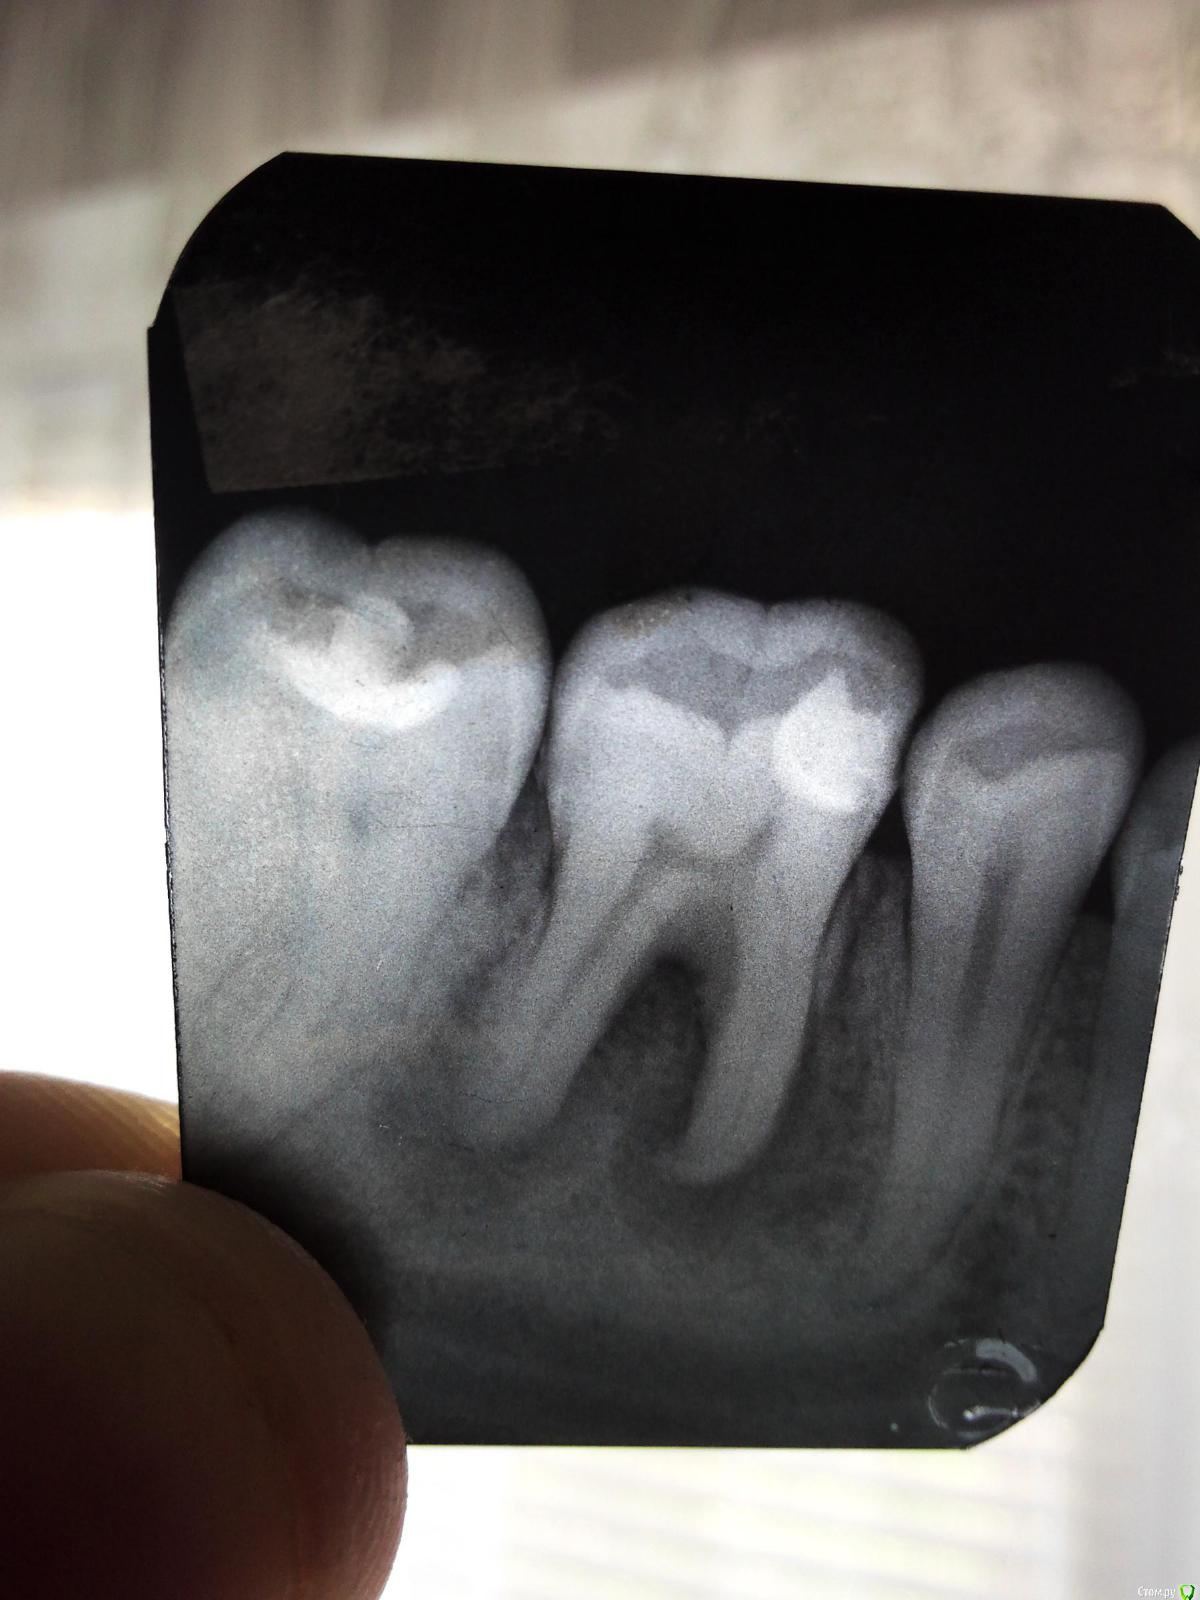

Karabas Опубликовано 2 мая, 2016 Автор Поделиться Опубликовано 2 мая, 2016 Добрый день. Прикладываю снимки.Сейчас в десне образовался еще один свищ, через которыйвыходит гной, очень неприятный запах(Сейчас уже думаю удалить зуб, хотя он по прежнему вообще не болит.Но выдавливать гной из десны несколько раз в день мне уже надоело(( Ссылка на комментарий

Karabas Опубликовано 31 марта, 2016 Поделиться Опубликовано 31 марта, 2016 (изменено) Добрый день!У меня нижний предпоследний зуб 2 раза пломбировали.Крайнее время под зубом начала вспухать десна и образовалась шишка,когда шишка лопнула из нее вылился гной.В общем сходил к стоматологу, сделали снимок зуба, там оказалась киста, которой по его словам 2-3 годаи стоматолог сказал, что зуб уже лечить смысла нету, либо ходить пока не выпадет или сильно не расшатается, либо говорит давай сразу его удалим, но так как зубвообще не болит и не шатается я удалять отказался.Но гной по прежнему каждый день из десны идет, но зуб вообще не болит и не шатается,с виду абсолютно здоровый.Скажите пожалуйста стоит ли сейчас удалять этот зуб, чтобы избежать каких либо дальнейшихосложнений? Либо все таки дождаться когда зуб начнет сильно шататься и идти удалять его? Изменено 31 марта, 2016 пользователем Karabas Ссылка на комментарий